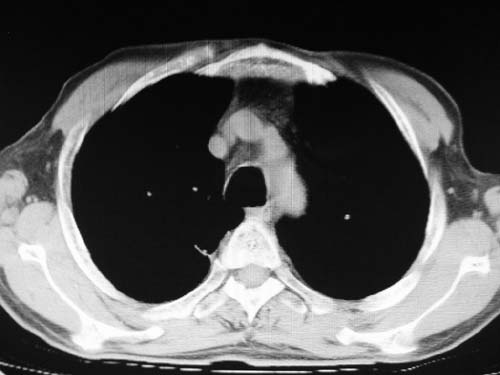

)考虑肺动脉扩张,右心室增大,主动脉弓段正常位弓后段明显变小(不会是动脉导客未闭吧,不知患者有何症状病史)0。2)右肺上叶继发性肺结核。3)右侧胸膜增厚、钙化,左侧胸膜反应。

肺动脉高压,左肺动脉瘤样扩张。

1)考虑左肺动脉瘤可能性大,建议增强。2)右肺上叶继发性肺结核。3)右侧胸膜增厚、钙化,左侧胸膜反应。

1)考虑肺动脉狭窄。2)右肺上叶继发性肺结核。3)右侧胸膜增厚、钙化,左侧胸膜反应。